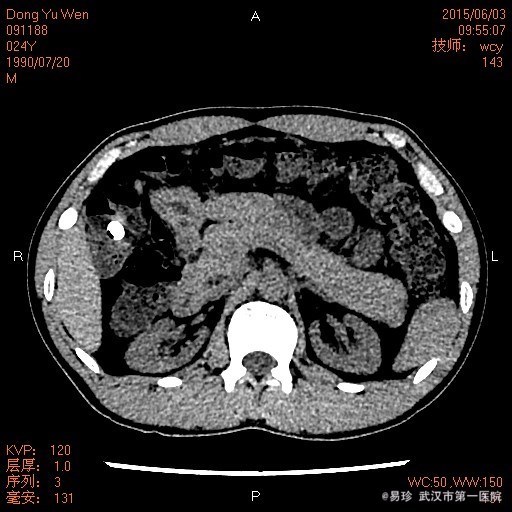

查体:生命体征平稳,听力下降,心肺听诊未见明显异常,腹软、无压痛,双下肢无水肿。 辅查: 泌尿系CT:双肾慢性肾病表现,双肾小结石,右肾轻度积液,右侧输尿管上段扩张,中下段显示不清。